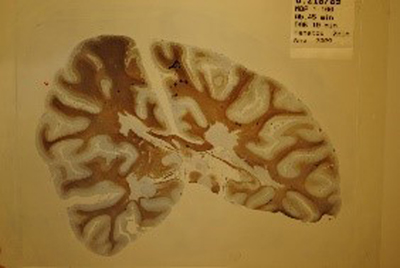

This photo of a brain section with grey and white matter and a brain tumour with a bleed (hemorrhage) was taken by Norbert Wey from a case I examined with a young colleague, Jens Pahnke, in 2002. (Department of Pathology, University Hospital Zurich, Switzerland)